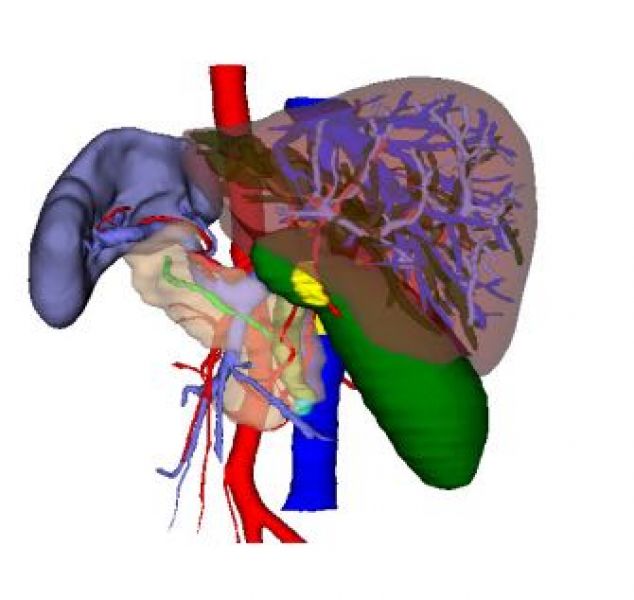

考虑到肝内错综复杂的解剖结构,明确病变肝脏与邻近重要管道组织的关系,医生们再次和患方沟通并取得理解和支持,利用最新的计算机多维数字图像处理技术以及多维测量技术和专业网络技术对其CT图像进行3D可视化处理,提供了数字化三维模型,医生们更清晰的了解病变器官及周围器官的立体组织结构和管道变异情况,制定了更为精准的手术方案。同时,为了避免手术过程中的医源性损伤,医生们为患者进行了术前模拟手术,决定逆向思维,优势右手为主操作,从穿刺孔的布局,术者的站位,助手的配合,麻醉师的操作...具体每一个操作细节均在模拟器上进行了模拟,并取得了理想的效果,坚定了术者的信心。

“镜面人”的成因是胚胎发育过程中的正常变异,是心、肺、胃、肝、脾、肠等内脏转位 180°,全部长反了位置,就像正常人在镜子中的影像一样,其概率约为百万分之一,在医学界较为罕见。正常人胆管炎发作表现为右上腹疼痛,放散至后背,“镜面人”患者却表现为左上腹部疼痛,同样向后背放散,该患者在州医院完成了影像学等检查,确认为一例典型的“镜面人”。通常行腹腔镜手术时,主刀医师和助手已形成固定的操作习惯和模式,而镜面像患者需反向搭配,手术顺序步骤和正常一样,习惯的改变有造成术中误伤周边脏器的可能,导致不良后果。针对“镜面人”的腹腔镜下解剖性肝切除手术,目前国内外文献鲜有报道,该手术得以顺利完成,得益于精确的术前设计,术前3D可视化有助于精确判断肝内重要的解剖标志,医生们针对术前资料细致的研究,熟悉了“镜面人”的肝内脉管的走行,精准把控切肝范围。遵循人体工程学原理,不断“反向思维”,针对术中具体操作难点进行术前模拟操作,并突破技术瓶颈,找到解决方案。术后医护合作,不断思考,为患者实施有效的加速康复管理措施,为类似罕见病例积累了宝贵的诊疗经验。

术前3D可视化(前面观,后面观)